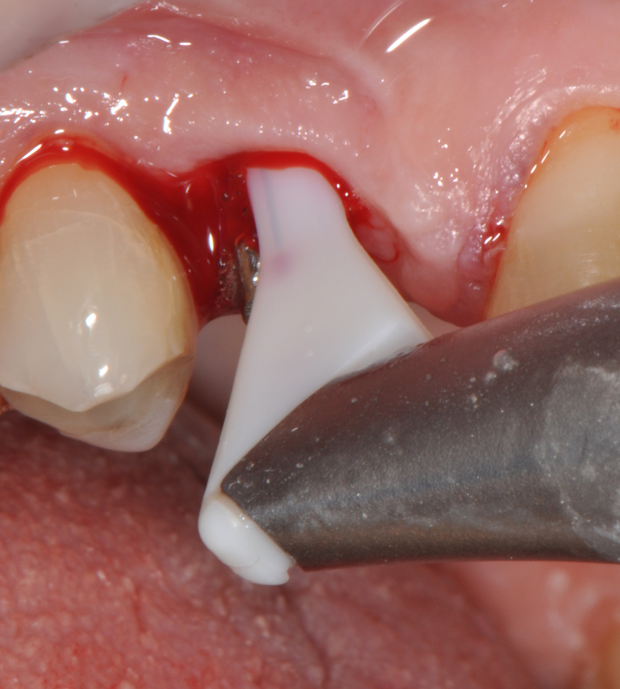

Second step of prevention can be carried out during the surgical phase: a correct positioning of the fixture can help the technician in constructing a correct prosthesis and, consequently, the periodontologist in checking the implant health, the hygienist in cleaning effectively the peri-implant area13 and the patient in keeping an high standard home-care. An ineffective care leads to the development of inflammatory reactions that can be kept hidden under the the prostheses and be unrevealed until their removal. (Fig.4) Particular attention should be given to reach an appropriate amount of keratinized peri-implant tissue: its presence can be beneficial for the maintenance of an adeguate oral hygiene.13 Long abutments and implant placement at sub-mucosal level cannot be considered a good choice from the periodontal point of view since they may create a deep probing depth since the very beginning of the implant-born restorations’ life.13

Fig.4: Case 1. Clinical appearance after the prosthetic crown removal.

So far, there is no scientific evidence supporting the efficacy of this coadjuvant. The tested protocol consist of a Multiple Anti Infective Non Surgical Therapy (MAINST) that involves the use topical 14% doxycycline to solve the peri-implantitis acute phase and, after 7 days, a session of Full Mouth Air Polishing Therapy (FM-EPAPT) through erythritol powder (Fig.7), a piezo-ceramic device with a PEEK tip (Fig.8), the curettage of internal pocket line (Fig.9) and a second application od Doxy. The patients were further followed with quarterly maintenance sessions carried on with the same FM-EPAPT protocol. Up to 12 months BOP and mean PD decreased significantly and successfully, accompanied by a gain of attachment level up to 12 months. The first case-series about MAINST is waiting to be published and the results are encouraging. Figure 10 and 11 show the healing at 6 and 12 months after MAINST protocol of the peri-implantitis case displayed at the beginning of this article (Fig.1,2,3,4) and figure 12-21 show a complete MAINST case.